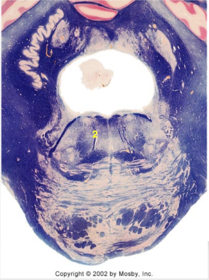

| Head of caudate | |

| Anterior commissure | |

| Thalamus | |

| Substantia nigra | |

| Optic tract | |

| Dentate nucleus | |

| Pons | |

| Longitudinal pontine fibers | |

| Uncus | |

| Superior cerebellar peduncle | |

| Red nucleus | |

| Corticospinal tract (dark) | |

| Pontine nuclei (pale) | |

| Transverse pontine fibers (dark) | |

| Inferior olive | |

| CTT | |

| Medial lemniscus | |

| Nucleus cuneatus | |

| Superior colliculus | |

| Inferior colliculus | |

| Optic nerve | |

| Cerebellum | |

| 4th ventricle | |